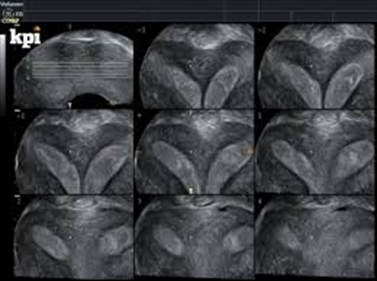

• Tomographic Ultrasound Imaging (ΤUI): Παρέχει απεριόριστη δυνατότητα στο να συλλέγει αξιόπιστες πληροφορίες για την απεικόνιση ανωμαλιών σε συγκεκριμένες περιοχές.

Όταν αναγνωρισθεί η περιοχή ενδιαφέροντος, τίθεται πλαίσιο οριοθέτησης και με σταθερή την υπερηχογραφική κεφαλή αρχίζει η εξέταση. Γίνεται αυτόματη σάρωση 360ο της περιοχής ενδιαφέροντος. Το τελικός αποτέλεσμα είναι η παρουσία 3 πλάνων, τα οποία μπορούν να μετατοπισθούν ή να περιστραφούν γύρω από τους άξονες x, ψ, z. Ο ανασχηματισμός των 3 εικόνων και η τελική σύνθεση μιας μόνο εικόνας προσφέρει ακριβέστερη μορφολογική εκτίμηση του όγκου του σώματος της μήτρας χωρίς να απαιτείται ιδιαίτερος χρόνος, μειώνοντας παράλληλα την δυσφορία αναμονής της ασθενούς.

Τα 3 πλάνα που εμφανίζονται στην οθόνη είναι:

α) το άνω αριστερό πλάνο (στεφανιαίο), «α», β) το άνω δεξιό πλάνο (οβελιαίο), «β», γ) το κάτω αριστερό πλάνο (εγκάρσιο), «γ». Στο κάτω δεξιό πλάνο εμφανίζεται η εικόνα «δ» μετά από τροποποίηση και επεξεργασία των 3 εικόνων («α», «β», «γ»).Για πληρέστερη αξιολόγηση του υπό εξέταση οργάνου και την επίτευξη του όσο το δυνατόν καλυτέρου αποτελέσματος απεικονιστικής ευκρίνειας, γίνεται χρήση ειδικών μεθόδων (modes):